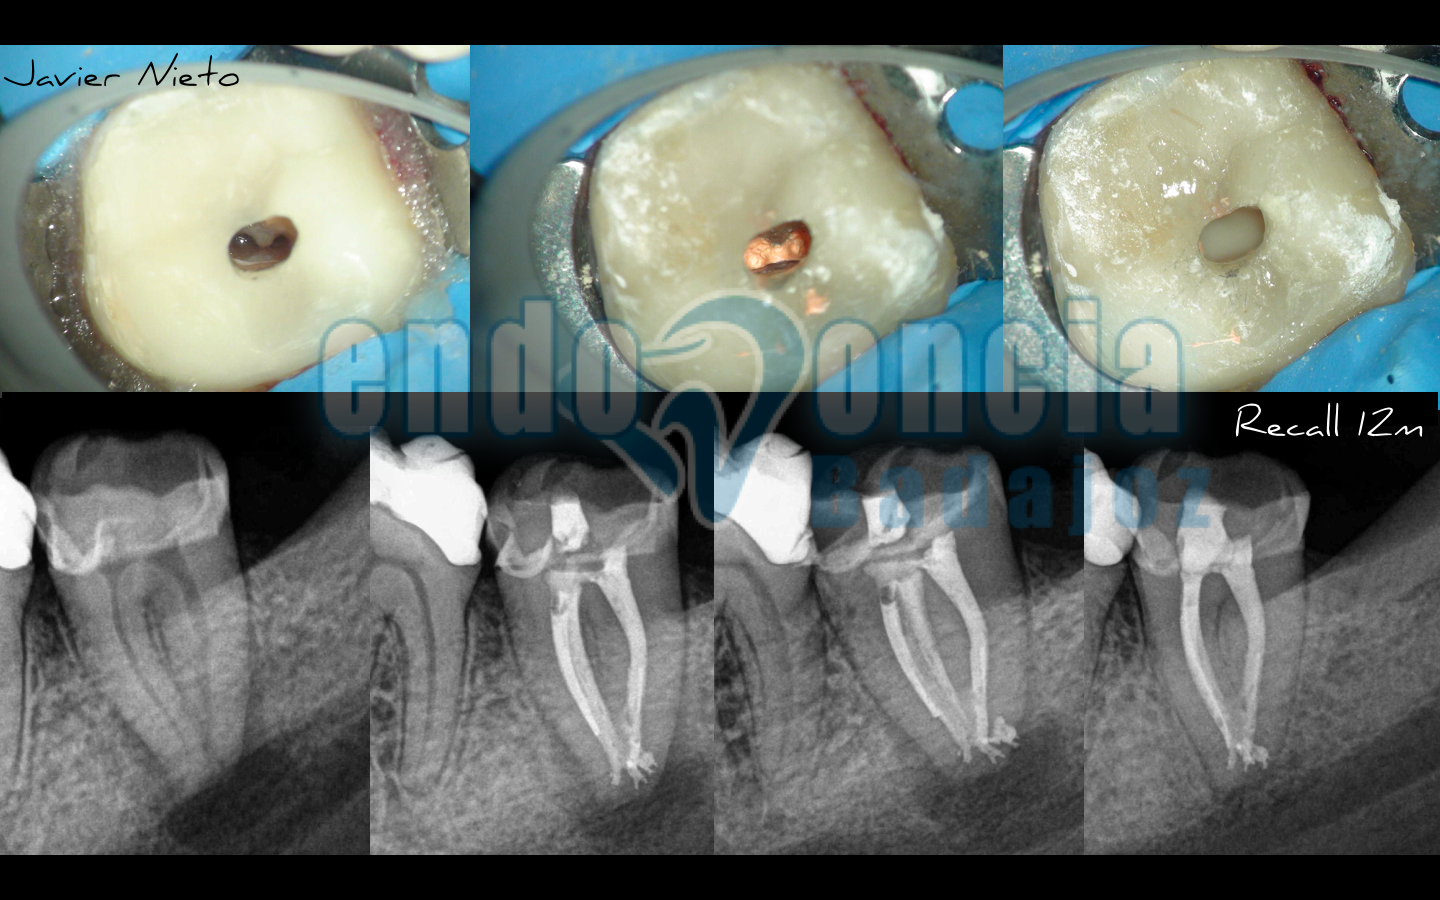

Anatomía de un 3.7

Subimos este casito de un 3.7, en el que intentamos ser lo más conservador posible, y que realmente, nos habría gustado que estéticamente fuese más bonito, pero que finalmente quedó tal y como veis. Comparto la opinión de que se trata de casos mucho más complicados y que pueden hacer que si no estudiamos bien el caso, puede que fracasemos por no tratar la anatomía de la mejor manera.

Al año, vemos el resultado de un tratamiento predecible.